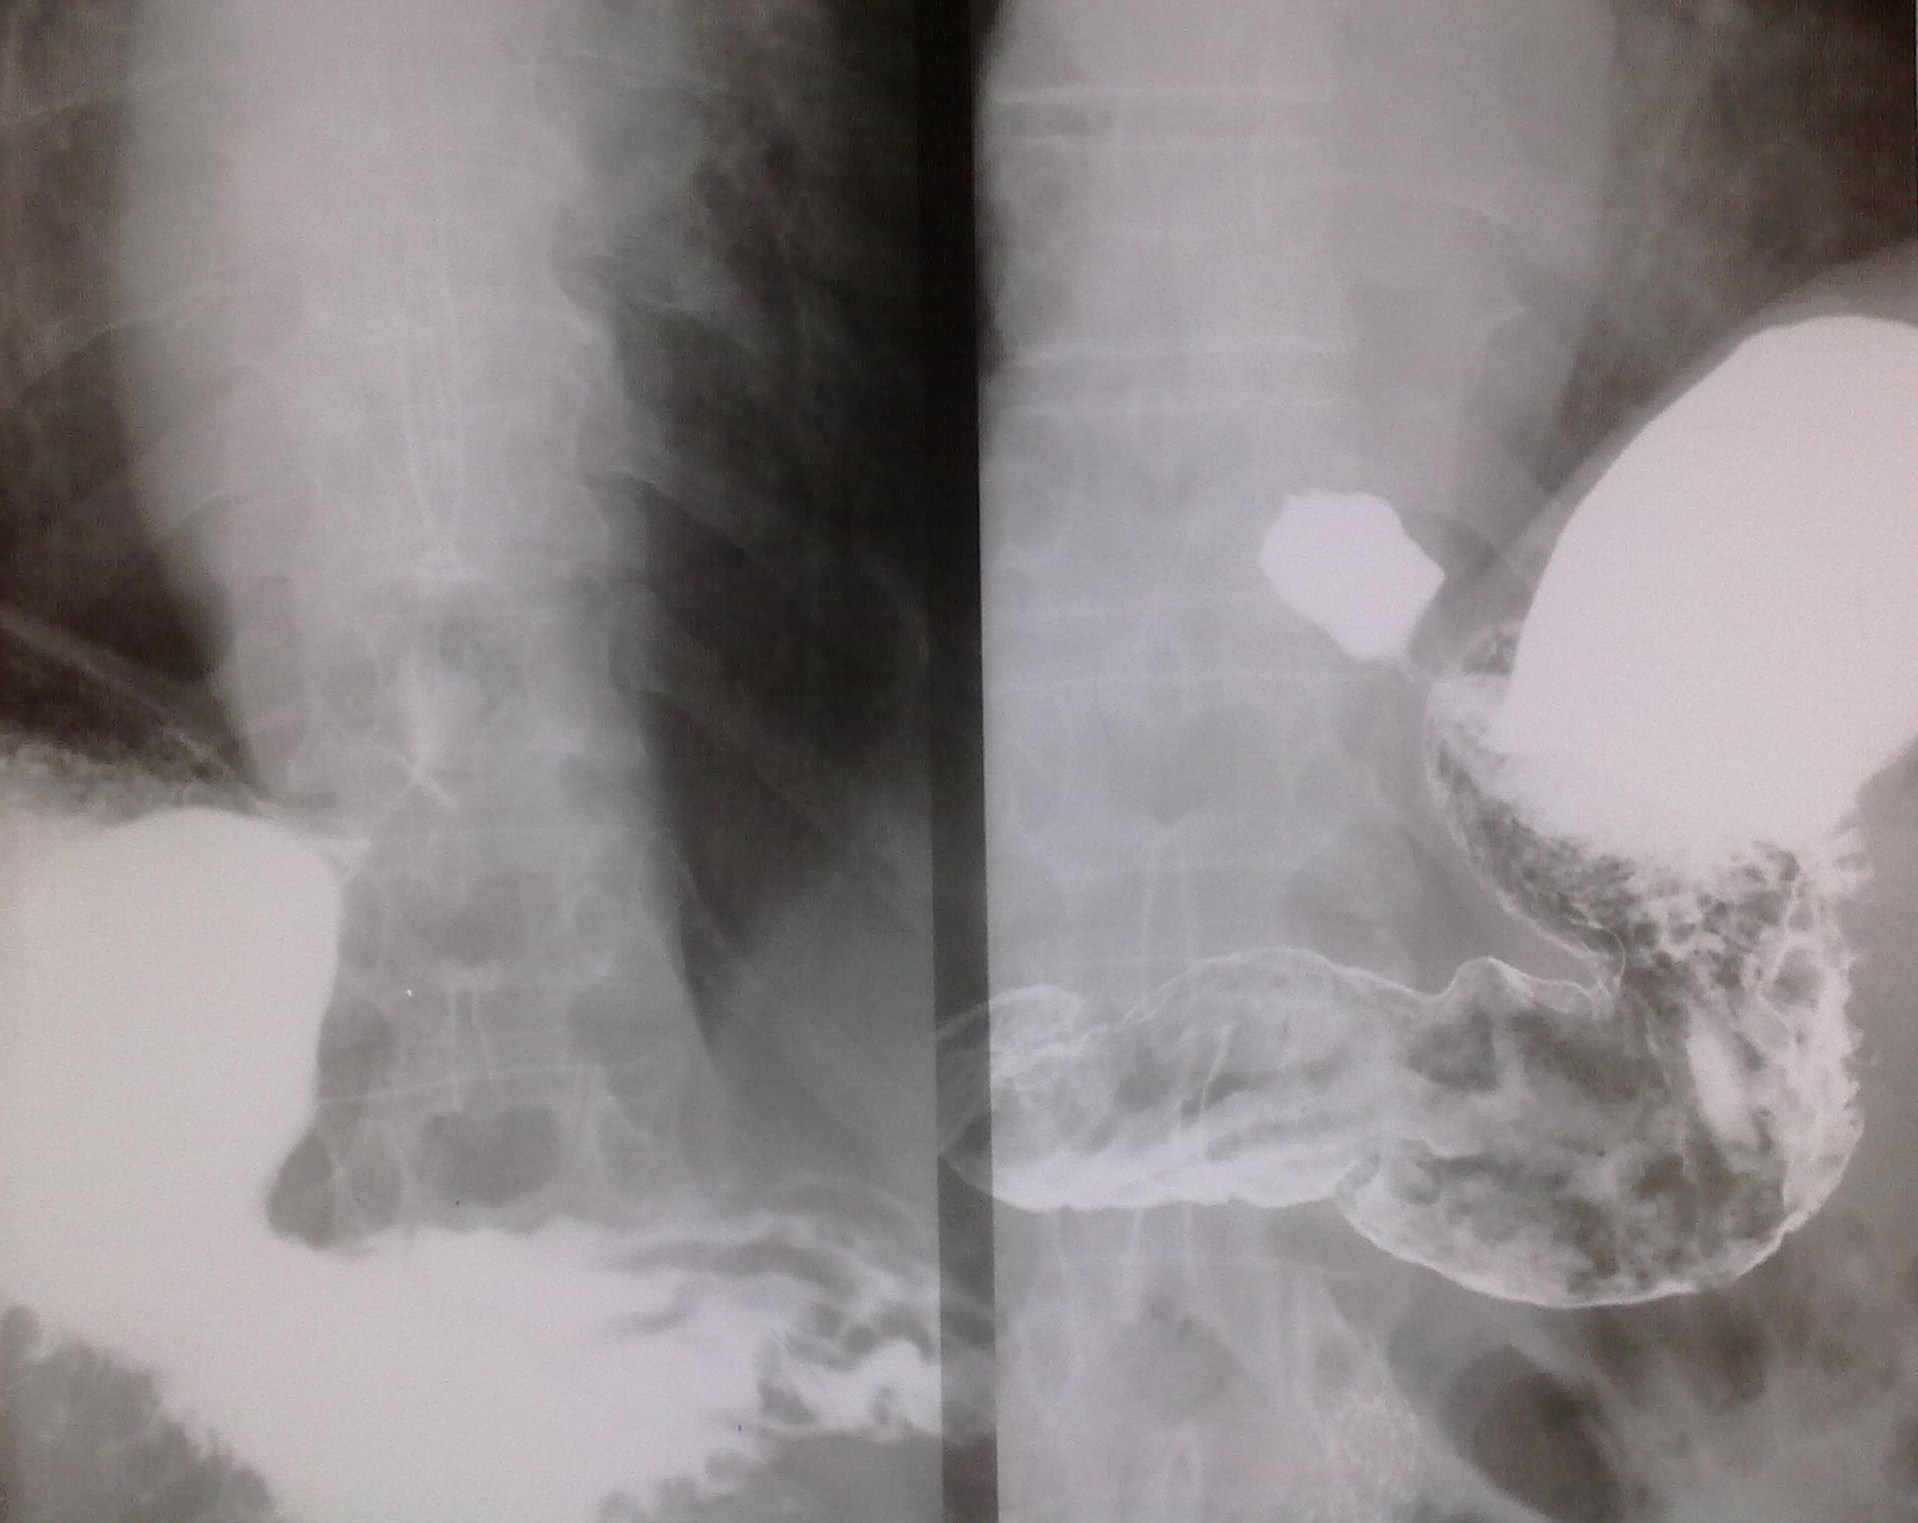

Ну, как Вы понимаете, по снимкам рельефа сторонний наблюдательно может напридумывать что угодно. Поэтому, если позволите, то по методике. Представлено 5 снимков. Каких нет? Нет прямого в вертикальном положении с контрастированной 12-перстной кишкой; нет лежа на животе с приподнятым левым боком и контрастированным пищеводом (именно в этой проекции определяется ГПОД), нет лежа на спине с приподнятым правым боком (для оценки пилоробульбарной зоны), нет левого бокового снимка стоя после снимков лежа (для оценки купола и задней стенки желудка). Снимок №4 (кроме того, что не контрастирована 12-перстная кишка) провоцирует больше вопросов, чем дает ответов: можно придумать дефект наполнения по малой кривизне в антральном отделе и пальцевое вдавление по большой по типу "перста указующего" (стрелки) И еще - гиперпластический гастрит, все-таки, достаточно редок, хронический гастрит, в основном, атрофический; неровность контура по большой кривизне в антральном отделе - является признаком хр гастрита (выход складок на контур); двуслойное содержимое луковицы 12-перстной кишки (газ и барий) - р-признаки бульбостаза (бывет еще 3-хслойное содержимое - барий-жидкость-газ) - косвенного признака патологии желчевыводящих путей.

Ну, как Вы понимаете, по снимкам рельефа сторонний наблюдательно может напридумывать что угодно.

Поэтому, если позволите, то по методике. Представлено 5 снимков. Каких нет? Нет прямого в вертикальном положении с контрастированной 12-перстной кишкой; нет лежа на животе с приподнятым левым боком и контрастированным пищеводом (именно в этой проекции определяется ГПОД), нет лежа на спине с приподнятым правым боком (для оценки пилоробульбарной зоны), нет левого бокового снимка стоя после снимков лежа (для оценки купола и задней стенки желудка).

Снимок №4 (кроме того, что не контрастирована 12-перстная кишка) провоцирует больше вопросов, чем дает ответов: можно придумать дефект наполнения по малой кривизне в антральном отделе и пальцевое вдавление по большой по типу "перста указующего" (стрелки)

И еще - гиперпластический гастрит, все-таки, достаточно редок, хронический гастрит, в основном, атрофический; неровность контура по большой кривизне в антральном отделе - является признаком хр гастрита (выход складок на контур); двуслойное содержимое луковицы 12-перстной кишки (газ и барий) - р-признаки бульбостаза (бывет еще 3-хслойное содержимое - барий-жидкость-газ) - косвенного признака патологии желчевыводящих путей.